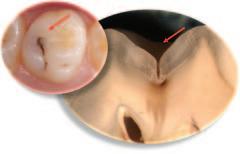

Visual examination for caries detection

Visual examination for caries using the merged-ICDAS system can be an important aid to minimally invasive dentistry.